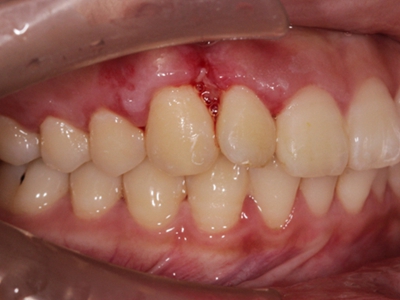

牙龈炎是发生于牙龈组织的炎症,患者可出现牙龈出血伴肿胀、发红、正常形态改变和偶尔不适等症状。本病主要由口腔卫生状况差导致,包括口腔不洁、牙菌斑等,诊断依据临床检查,治疗包括专业牙齿清洁和加强家庭口腔卫生。

牙龈炎可先引起牙齿与牙龈之间的沟(龈沟)加深,然后牙龈充血,炎症围绕一个或多个牙齿,伴牙龈乳头肿胀和易出血。一般无痛,可自行消退,也可维持轻度炎症数年。

牙龈炎常见的病因是口腔卫生差,不良的口腔卫生使牙菌斑沉积于牙齿与牙龈之间,造成龈沟加深,另外牙结石、不良修复体等也可造成牙龈炎的发生。